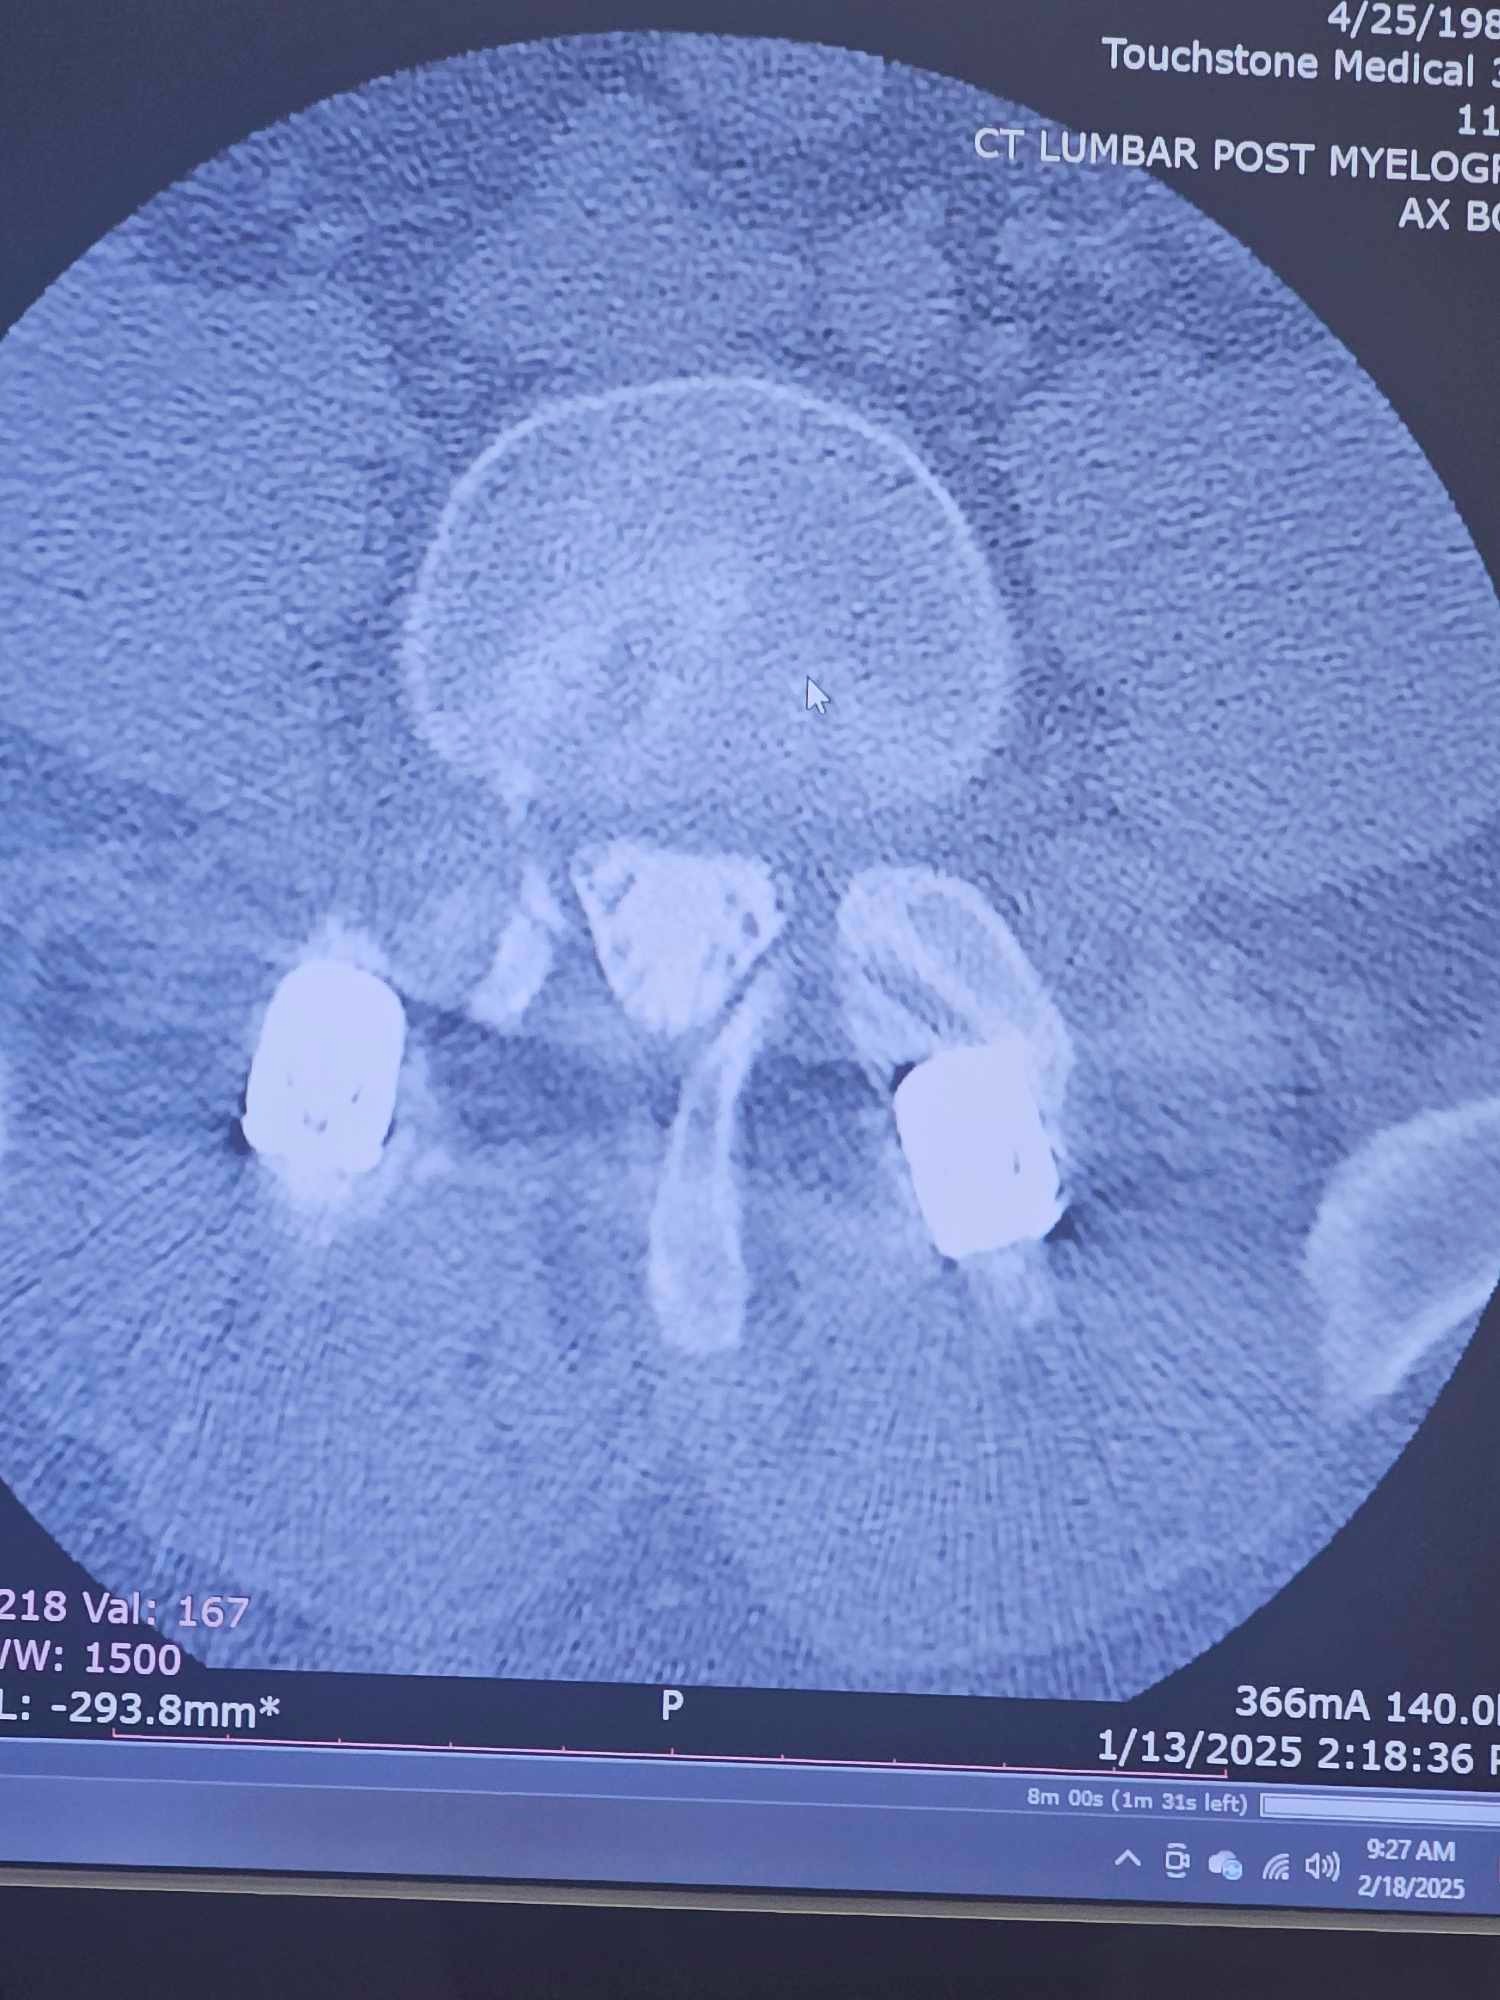

My name is Sonny Gentry. I was in a wreck 3 years ago at no fault of my own at 70 mph. As time passed by, my neck and lower back began to deteriorate. After waiting a very long time, I finally had surgery on July 15th, 2024, and that was a complete fail. I am only able to stand for 30 minutes at a time, and meds only help very little. Just really needing help with bills and meds as I am unable to work after all these years of working. Please feel in your heart to help. If CashApp $southerneuf81 or Venmo @sonny-gentry25 is better for you, then that's great too.